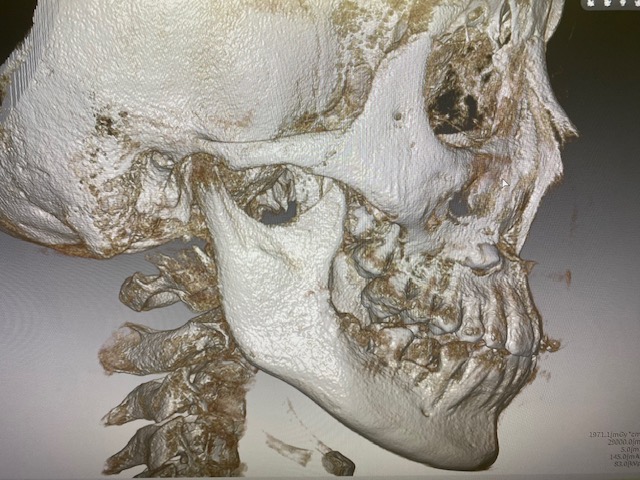

④ CTスキャン(ケースにより未撮影の場合あり)

⑤ その他、必要に応じCTスキャンを利用した気道分析

(👆 当院設置のCTスキャン画像)